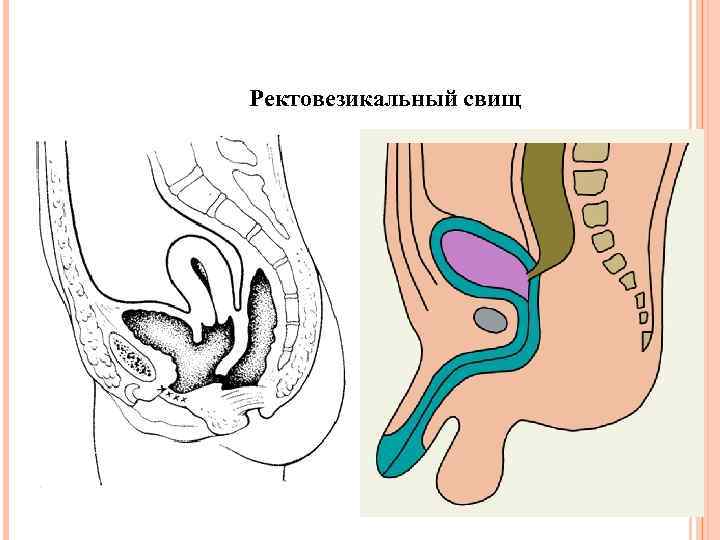

Ректовезикальный свищ

Ректовезикальный свищ